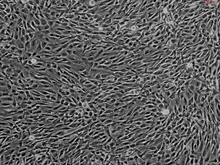

Human Sertoli Cells, Passage 1

Cryopreserved Primary Cells, Single Donor

Sertoli Cells (SerC) are essential for testicular development, spermatogenesis, and formation of the blood-testis barrier. SerC limit the passage of substances such as hormones and nutrients to the adluminal compartment of the seminiferous tubules. In addition to forming the blood-testis barrier, SerC also provide the main structural support for the seminiferous tubules and protect the germ cells from the immune system. Aberrant SerC proliferation can contribute to the development of male reproductive disorders such as testicular germ-cell cancer, cryptorchidism, hypospadias, and low sperm count. SerC proliferation is in part controlled by follicle-stimulating hormone (FSH) and thyroid hormone (TH), where FSH drives proliferation and TH promotes a more quiescent state. Cultured Human SerC are a useful in vitro model to better understand testicular dysgenesis syndrome and to develop treatments for male reproductive disorders. (SC4520)